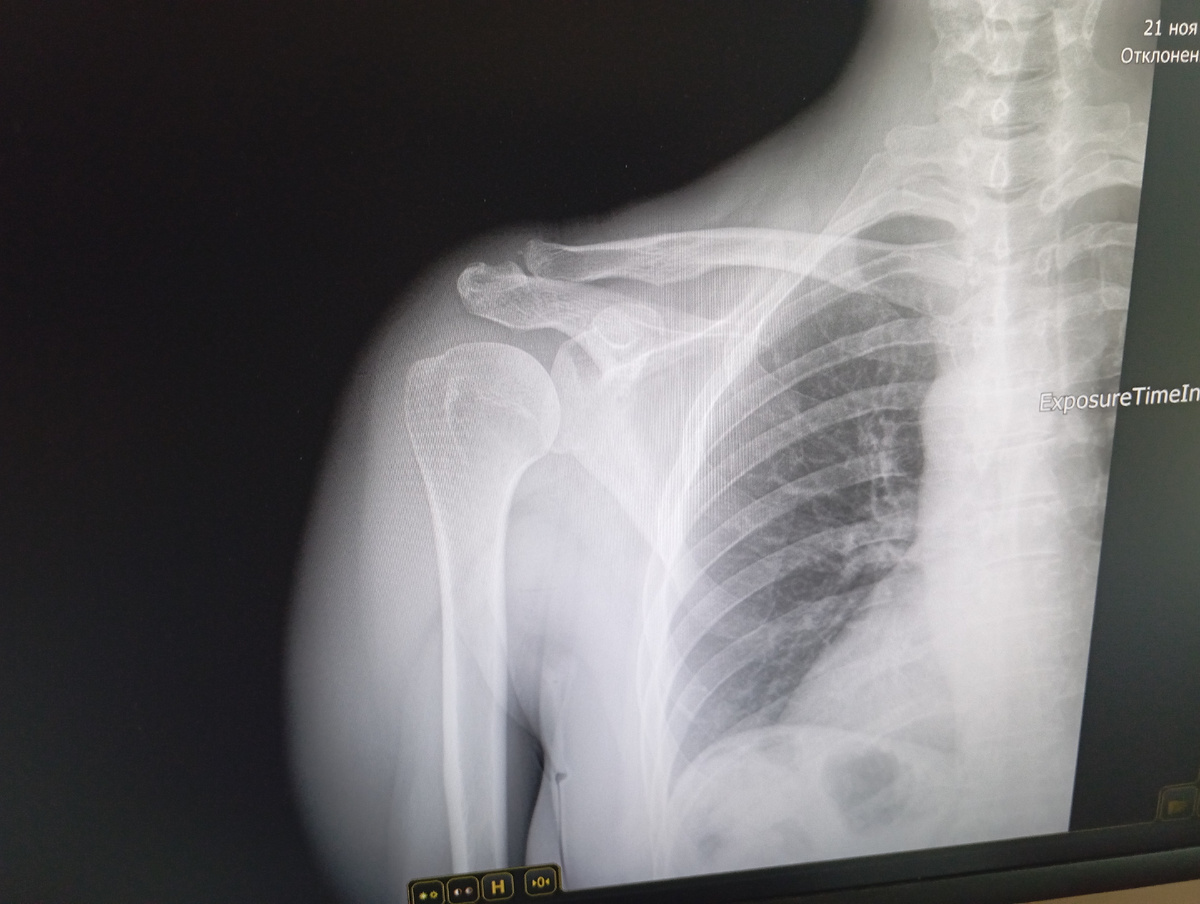

Очень много покупок еще и рентген сегодня сделала.. Диагноз - меня точно не порадовал..

Ну и раз поехали - сделала рентген..

Снимок у меня сфоткан на телефоне с монитора, потому что распечатать его там не могут, а пожилой дедок который описывает - не сильно в ладах с техникой... Когда приду к терапевту - зайду и уточню, а может и у терапевта уже будет в компе с расшифровкой, она и распечатает. Вот вам и прелесть жизни в станице - принтеры только у избранных)

Снимок и вам покажу, может меня читает тот, кто в этом понимает и расшифрует... Уменьшать фото не буду -

Мы с мамой конечно смотрели, она чето в шее нашла, то что плечо сильно вспухши - это давно так, как болеть начало.. В целом - ничего нам непонятно по фото.. А мама кстати - раньше работала в больнице в Питере как раз рентген-лаборантом.. Тогда и аппараты другие были и снимки сами проявляли в комнате с красным светом, и пенсия по вредности была с 45 лет..

Ну и еще только что пришла расшифровка рентгена на госуслуги..

Быстро погуглила, ДОА это Деформирующий остеоартроз, у меня 1-2 стадия, всего три стадии и третья самая плохая..

Я родственнице в Питере фото скинула, она на КТ в больнице работает, спросит там у местных врачей их мнение.. Ну и если вы в курсе что это и с чем его едят - напишите плиз.. Чето я от слова артроз расстроилась уже..

Теперь надо погуглить, подходит ли мне это лекарство за 5 тыщ, сегодня мне лениво гуглить, за выходные успею. Не очень нравится что артроз а не артрит, вроде артроз это сильно хуже... Ладно, будем посмотреть, как говорится..